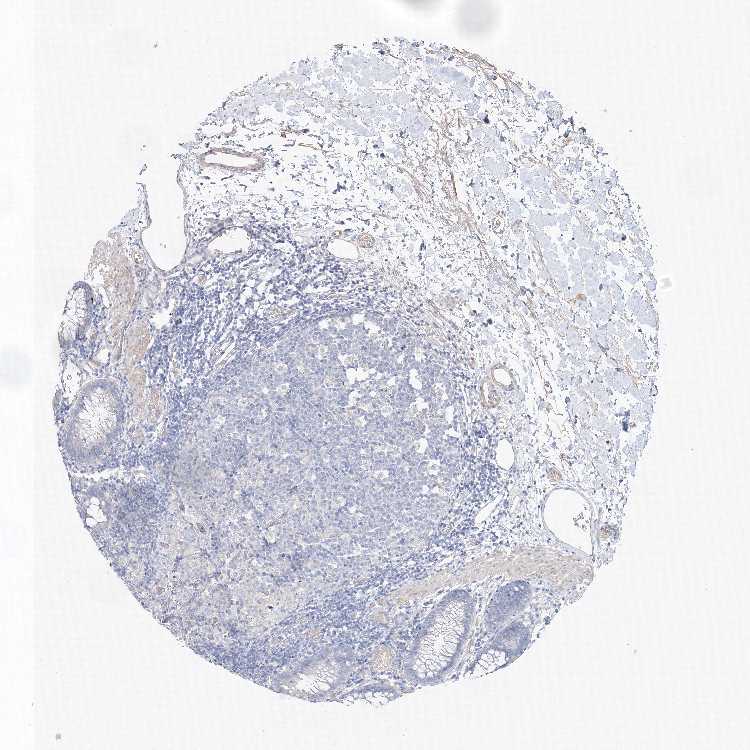

Antibody staining in the annotated cell types in the current human tissue is reported as not detected, low, medium, or high. This score is based on the staining intensity and fraction of stained cells.